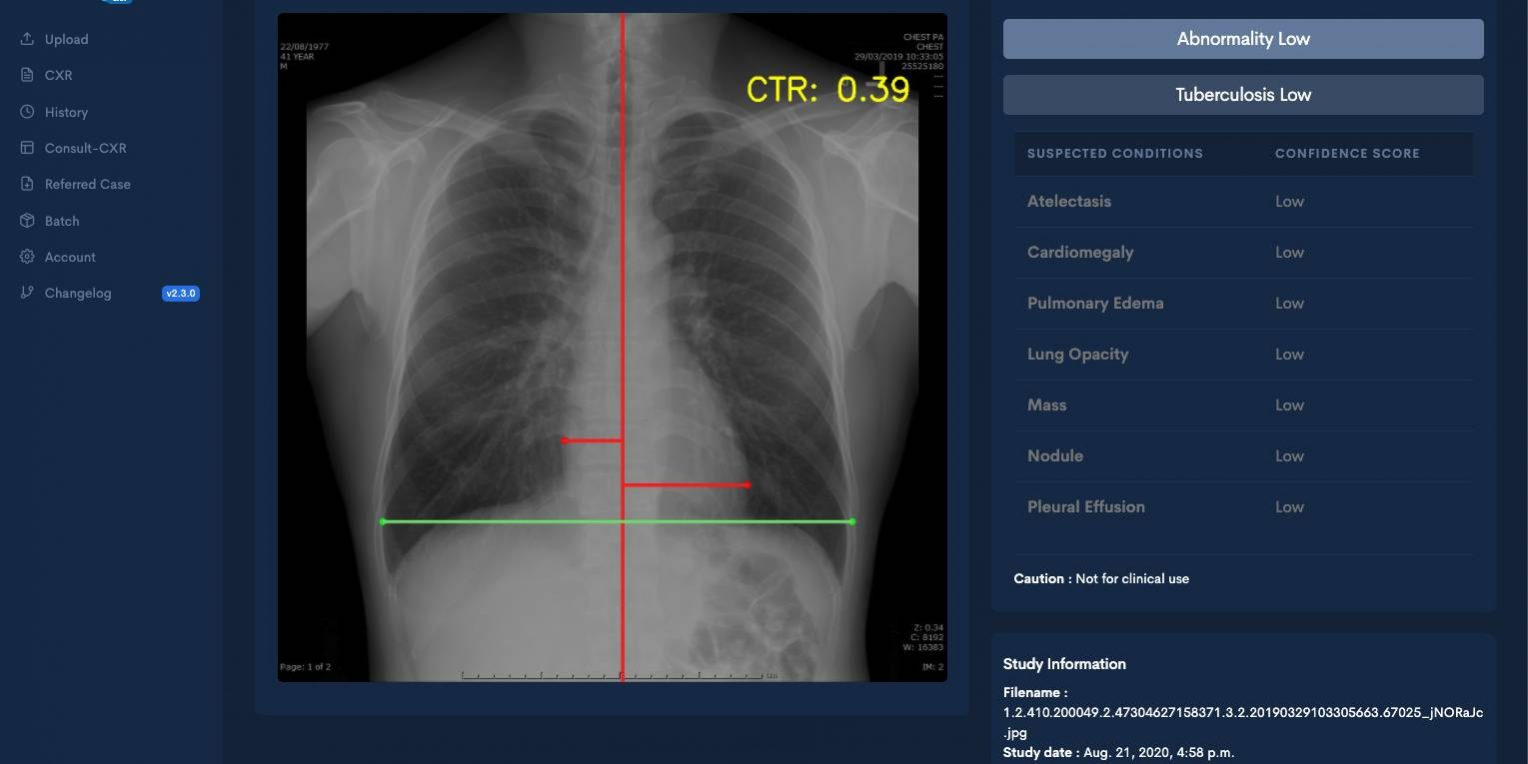

ดร.วราสิณี ฉายแสงมงคล อาจารย์ประจำสถาบันวิทยาการหุ่นยนต์ภาคสนาม (FIBO) มหาวิทยาลัยเทคโนโลยีพระจอมเกล้าธนบุรี (มจธ.) กล่าวว่า ระบบปัญญาประดิษฐ์ของอินสเป็คทรา ซีเอ็กซ์อาร์ สามารถคัดกรองความผิดปกติที่พบทั่วไปในภาพถ่ายรังสีทรวงอกได้ถึง 8 สภาวะ โดยแพทย์ผู้ใช้งานสามารถเข้าถึงได้ผ่านหน้าจอของแพทย์โดยไม่ต้องเปลี่ยนแปลงขั้นตอนการทำงานเลย หรือสามารถเข้าถึงได้ผ่านเว็บแอปพลิเคชันบนมือถือ หรือ แท็ปเล็ตที่มีระบบการรักษาความปลอดภัยสูง ซึ่งจะทำให้โรงพยาบาลที่ขาดแคลนรังสีแพทย์สามารถเข้าถึงบริการแพทย์ผู้เชี่ยวชาญได้มากขึ้น ช่วยให้มีโอกาสการตรวจพบความผิดปกติของปอดในระยะเริ่มต้นสูงมากขึ้น

หลักการทำงานของปัญญาประดิษฐ์ของโครงการนี้เป็นลักษณะ Deep Learning คือ Convolutional Neural Networks ที่เป็นที่นิยมในการใช้ประมวลผลภาพ โดยใช้ปัญญาประดิษฐ์มาทำงานร่วมกันหลายตัวเพื่อให้สามารถตรวจจับรอยโรคและช่วยแพทย์ได้อย่างครอบคลุม ยกตัวอย่างเช่นปัญญาประดิษฐ์ที่ทำหน้าที่จำแนกภาพว่ามีรอยโรคอะไรบ้าง เมื่อพบรอยโรคจะทำการไฮไลท์เพื่อให้แพทย์สามารถสังเกตเห็นได้ง่ายขึ้น อีกทั้งยังทำการคำนวณอัตราส่วนระหว่างปอดและหัวใจเพื่อตรวจวัดสภาวะหัวใจโตได้โดยอัตโนมัติ และคิดคำนวณความมั่นใจในการแสดงผลขอแต่ละรอยโรค รวมถึงมีปัญญาประดิษฐ์ตัวอื่นๆ ที่สนับสนุน การทำงานของระบบ เช่น การประมวลผลภาษาธรรมชาติในรายงานของรังสีแพทย์ เป็นต้น

“ปัญญาประดิษฐ์ตัวเดียวไม่เพียงพอต่อการใช้งานที่ซับซ้อนอย่างงานทางการแพทย์ จำเป็นต้องพัฒนาและเพิ่มเติมอีกหลายฟีเจอร์เพื่อเพิ่มความแม่นยำของระบบ เช่น การคัดกรองวัณโรค AI ต้องคำนวณคะแนนความผิดปกติออกมาอย่างแม่นยำโดยการดูจากสถิติประชากรประกอบด้วย หรือ การฝึกและให้ข้อมูลกับ AI ไปไฮไลท์จุดต่างๆ ที่พบรอยโรค หรือ AI ที่ช่วยคัดภาพเสีย และ AI ที่อ่านโรคที่เฉพาะเจาะจง เช่น โรคปอดแฟบ เป็นต้น” ดร.วราสิณี กล่าว

สำหรับความแม่นยำในการตรวจจับโรคโดยรวมอยู่ที่ประมาณ 90% มีงานวิจัยเชิงสถิติที่รองรับว่าผลของระบบได้ผ่านการทดสอบแบบครอบคลุมและระมัดระวังแล้ว จึงทำให้ระบบนี้ได้รับการยอมรับจากรังสีแพทย์ว่าช่วยให้สามารถอ่านภาพเอกซเรย์ได้เร็วขึ้น และแม่นยำขึ้นจริง